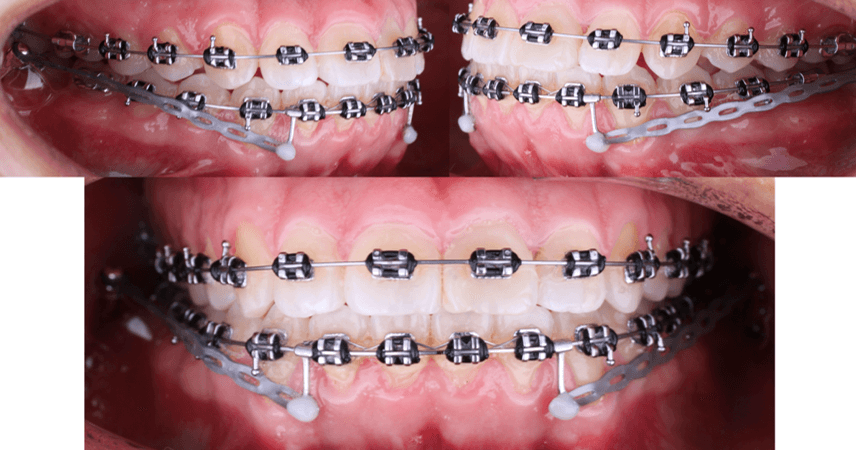

Decima cita. Colocación de mini implantes en el shelf mandibular de manera bilateral. Marca TD medida 2x12 con perfil transmucoso. Arco 16x22 nitinol superior. Arco 16x22 acero inoxidable inferior. Ligadura metálica de seguridad en 42-41-31-32. Brazos crimpables bilaterales en distal de laterales inferiores. Cadena elástica de los crimpables a los mini implantes con una fuerza de 150gr inicial.

Fig 11. Seguimiento fotografico

Doceava cita: Arco 17x25 acero inoxidable superior. Mismo arco, misma biomecanica en inferior. Despues de la colocacion de los mini implantes, el mini implante del lado derecho se desalojo un mes y medio despues de su insercion. Es esta cita se reinserto el mini implante en el shelf mandibular derecho; se cargaron ambos mini implantes con una fuerza de 150gr.

Fig 12. Seguimiento fotografico